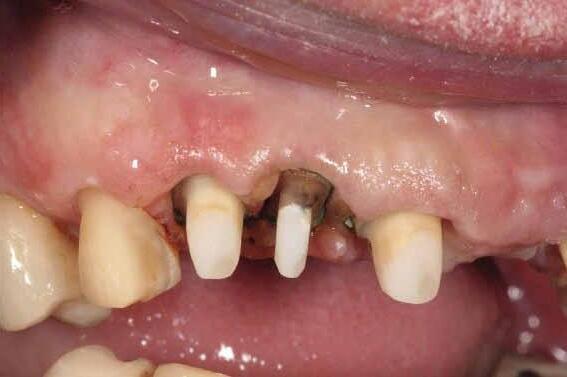

This case was performed by Dr Homa Zadeh, DDS, PhD, a respected leader in periodontology and implant dentistry. Dr Zadeh’s approach emphasizes biologically driven protocols and evidence-based techniques, making this case a strong example of clinical excellence using the Tapered Pro Conical system. It involves the replacement of two front anterior teeth after they fractured off and the full restoration process.

Fig 1. Patient anterior situation. Two anterior crowns fractured off.

Fig 2. Intraoral radiograph indicating tooth structural loss extent.

Fig 3. Provisional restorations on central incisors and gingival images. The gingival contours were optimal, and the gingival phenotype was thick.

Fig 4. Alveolar bone imaging. The alveolar bone was intact, and the alveolar crest was approximately 4mm apical to the restorative margin.